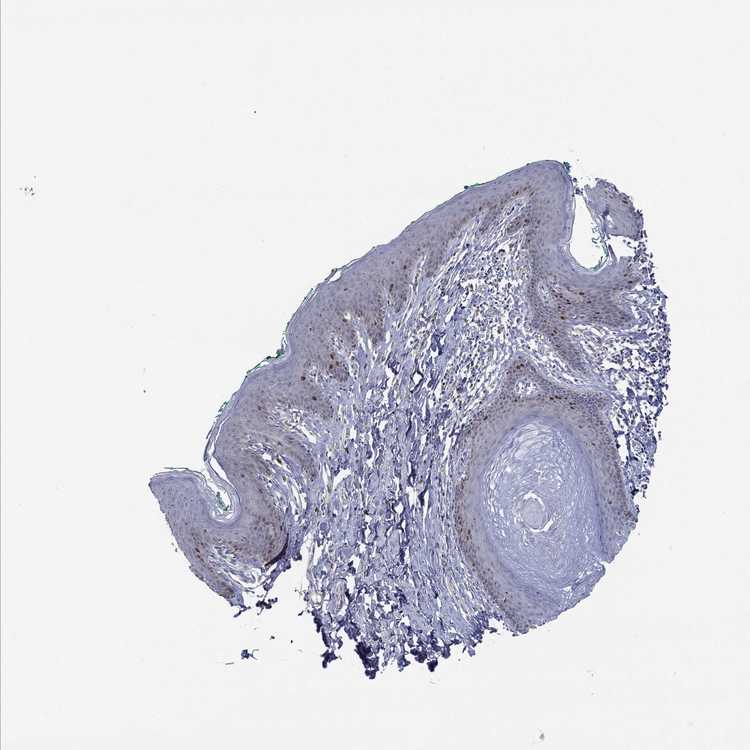

SKIN 2 - Antibody stainingi

Antibody staining in the annotated cell types in the current human tissue is reported as not detected, low, medium, or high, based on conventional immunohistochemistry profiling in selected tissues. This score is based on the combination of the staining intensity and fraction of stained cells.

Each image is clickable and will lead to virtual microscopy that enables deeper exploration of all samples and also displays staining intensity scores, fraction scores and subcellular localization as well as patient and tissue information for each sample.

Antibody HPA078816

Epidermal cells Low